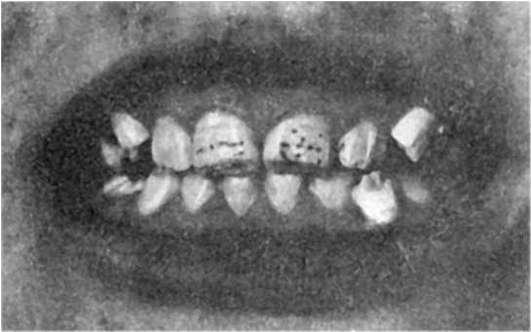

Различают 4 степени флюорозного поражения зубов: I степень - очень слабое поражение, при котором с трудом обнаруживаются единичные, мелкие фарфороподобные или меловидные пятна и полоски, расположенные на губной, язычной половине поверхности зуба и охватывающие не более 1/3 его поверхности.II степень - слабое поражение: видны фарфороподобные и меловидные пятна и полоски, занимающие около половины поверхности коронки зуба. Встречаются также и пигментированные пятна, но поражение локализовано только в эмали и не касается дентина. III степень - умеренное поражение: наблюдаются сливные пятна, занимающие более половины поверхности зуба (рис. 350). Пятна темно-

841

желтого и коричневого цвета. Разрушается не только эмаль, но и дентин. IV степень - сильное поражение, при котором образуются единичные и множественные эрозии эмали разной формы - как бесцветные, так и пигментированные (от желто-коричневой до черной окраски). При поражениях III и IV степени наблюдаются выраженные расстройства минерализации, вследствие чего зубы становятся хрупкими, ломкими, легко стираются и разрушаются.

Рис.

350. Флюороз. Множественные пятна на поверхности зубов (по А.А. Жаворонкову)